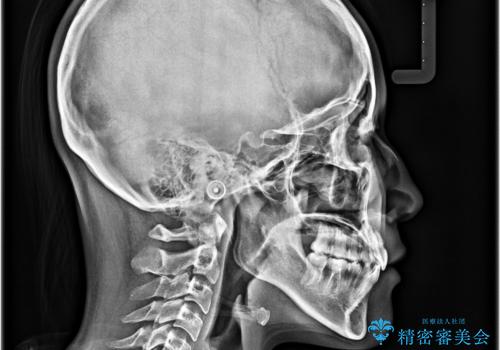

単純に上下左右の第一小臼歯4本を抜歯して口元の突出感を改善することも考えられましたが、上顎骨よりも下顎骨の幅が広いため、より良い咬み合わせを達成することを目的として、急速拡大装置を用いて上顎骨を拡大することとしました。

歯列矯正では基本的に骨格を改善することはできませんが、急速拡大装置(MARPE)を使用することで上顎骨を側方に拡大させることができ、咬合状態を大きく改善することができます。